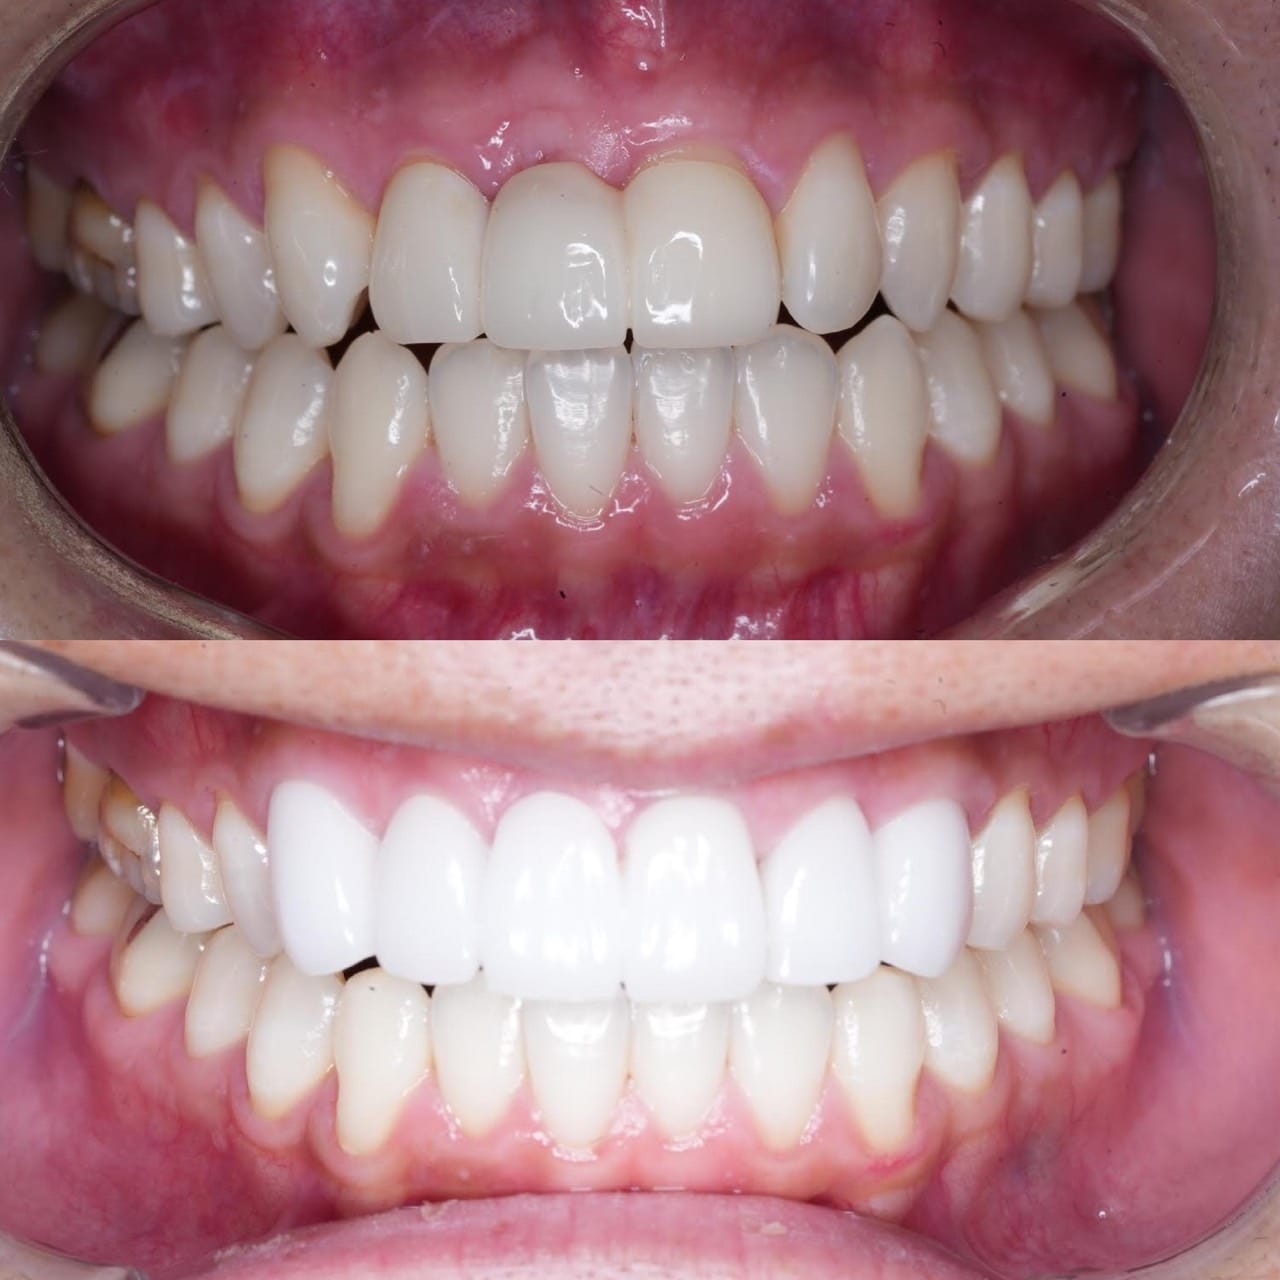

「ずっと放置してしまっていた。今回はちゃんとしっかり治したい」ということで、強い意志をもって来院してくださった患者様の症例です。

インプラント治療、セラミック治療、歯周病治療により、審美性と機能、咬みあわせの再建を行いました。

患者様は咬みあわせの確立により、食事もしやすく、普段の顎関節の状況も良くなり、機能の回復にも満足してくださり、また審美性も喜んでくださいました。

放置期間が長くだいぶ骨が溶けてしまっていたので、前歯部のインプラントは骨の再生療法などが必要だったりしましたが、患者様が治療への前向きな姿勢をだしてくださっていましたので期間も最短で終わりました。

一度放置してしまうと、億劫になってしまってなかなか行動に移すのは難しいと思いますが、少しでも早く治してあげた方が毎日の食事も楽になりますし、お顔の見栄えもお顔の骨格の歪みも改善します。